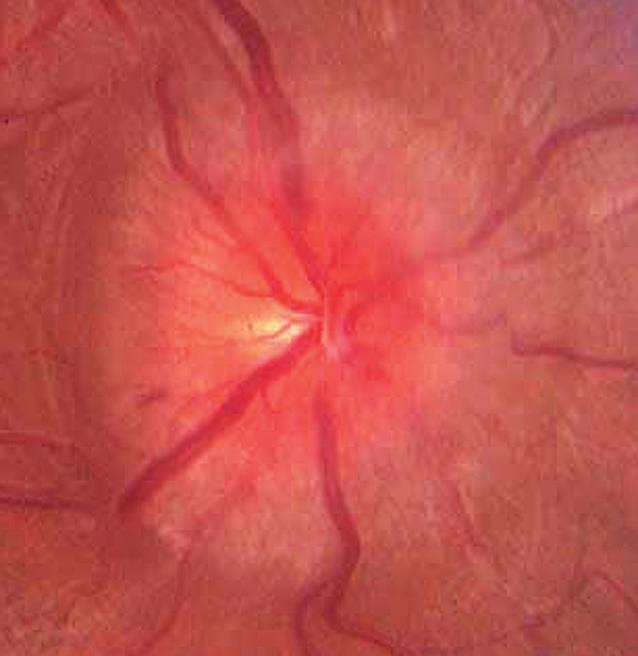

Bilateral disc swelling

10. Bilateral disc swelling could be papilledema (disc swelling due to raised intracranial pressure). The first investigation should be urgent (same-day) magnetic resonance imaging (MRI) plus magnetic resonance venography (MRV) to exclude a brain tumor or dural venous sinus thrombosis (see p. 120) (Fig. 1.10).

1.10 This 38-year-old man presented to an ophthalmic emergency department complaining of blurred vision and headaches. Examination revealed visual acuity 20/20 right and left and bilateral moderate disc swelling A, B. Because vision was good and there were “no other neurologic signs”, the patient was allowed to go home and was scheduled for neuro-imaging as an outpatient. Two days later, while driving, the patient experienced a generalized seizure, resulting in severe injuries to himself and another driver. MRI revealed a brain tumor which was found at surgery to be an astrocytoma. For how to safely manage disc swelling with normal vision, see p. 110.